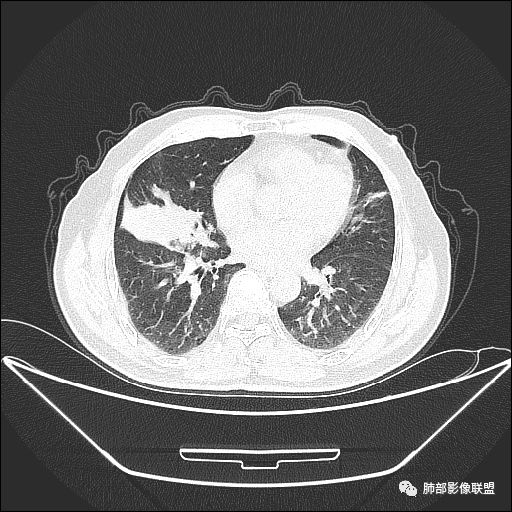

入院CT

老年男性,亚急性病程,咳嗽咳痰。右肺中叶团片影,外朝内分布,大部分边界清楚平直,内侧支气管进入,团片影见低密度坏死区,强化明显,延迟强化,血管破坏不明显,符合爬行征5个特点:

1.肺外周生长。

2.外侧部分体积大于内侧。

3.病变最大径与肺的纵轴及水平面任何一条轴线不平行。

4.病变内侧支气管通畅。

5.病变区域肺容积无缩小。

双侧肺门及纵隔淋巴肿大并可见钙化。考虑结核,但部分边缘膨隆,肿瘤待排。

老年男性,因“咳嗽咳痰1月余。”入院。病程中咳嗽咳痰,咳黄白痰,间断咯少许鲜红色痰血。PPD阳性。胸CT:右肺中叶外侧段支气管管腔阻塞,大片实性病变,病灶边缘光滑,部分边缘膨隆,可见分叶,肺门及纵隔可见肿大淋巴结,并可见钙化。增强可见病灶明显强化,而且延迟强化明显,病灶内多发低密度区,内见血管影,血管变细、部分血管破坏。考虑恶性病变可能性大,鉴别慢性肉芽肿性病变。

右肺中叶外侧段管腔阻塞、实性病变,病灶边缘光滑,可见分叶,肺门及纵隔可见肿大淋巴结,并可见钙化。增强可见病灶内多发低密度区。

老年男性,咳嗽、咳痰1月余,间断血痰。PPD阳性。

胸CT:跨叶大肿块,主体在中叶,右中叶外侧段支气管阻塞,病灶部分边缘膨隆,可见分叶,部分边缘平直,肺门及纵隔可见肿大淋巴结。增强病灶不均匀强化,延迟强化明显,病灶内多发低密度区,内见血管飘浮,部分血管变细、模糊。考虑:恶性病变可能性大,大细胞?淋巴瘤?鉴别慢性肉芽肿性病变。

右肺中叶软组织肿块,外围向内生长,叶间胸膜向前内移位,肿块近肺门侧跨叶,中叶外侧段支气管截断,密度不均匀,双侧肺门及隆突下见肿大淋巴结,增强后呈中度不均质强化,肺动脉供血,多发坏死区,边界尚清,坏死区域内见结构,结合病史考虑恶性,鉴别诊断1结核,爬行征是沿支气管树分布,外宽,内窄,周围有卫星灶,内气管狭窄后扩张,此例沿叶间胸膜长轴分布,气管有截断,不典型。2炎性肉芽肿,符合的地方下方层面增强后延迟性轻度环形强化,不符临床无发热等急性感染病史,实验室指标不符,病灶周围渗出及慢性炎性改变有,不明显。